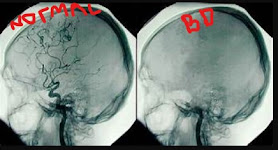

Tuesday (July 4): Happy Fourth of July! Today I spent the morning catching up with family via phone and updating them on my amazing experiences. I then followed those conversations by reading my packet on Brain Death, what it is, and how to explain brain death to other people. Previously, I knew that brain death was different from a coma however, this reading really helped me expand on my knowledge and what actually causes brain death. I will attach photos that helped me understand what brain death was but in short, brain death is caused by the lack of blood flow from going beyond the brain stem. You're brain stem is divided into three portions (the midbrain, medulla, and pons). The medulla portion of your brain stem is what controls respiration (breathing), so when blood flow stops then your brain cannot complete the processes that create meaningful life.